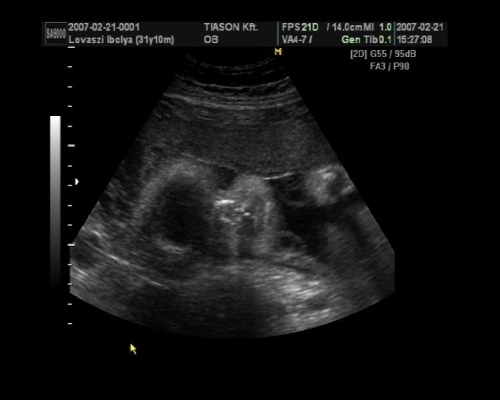

, de ami fura volt, a szívét a pocakom bal oldalán középtájban éreztem, felette pedig folyamatos rugdosást, vagy kalimpálást, De a másik oldalon ugyanott szintén... Lehet, hogy keresztben van???? De a múltkor már lent volt. Na kíváncsi vagyok kedden mit mutat az UH. Dehát azt csak lehetne látni rajtam, ha keresztben lenne...